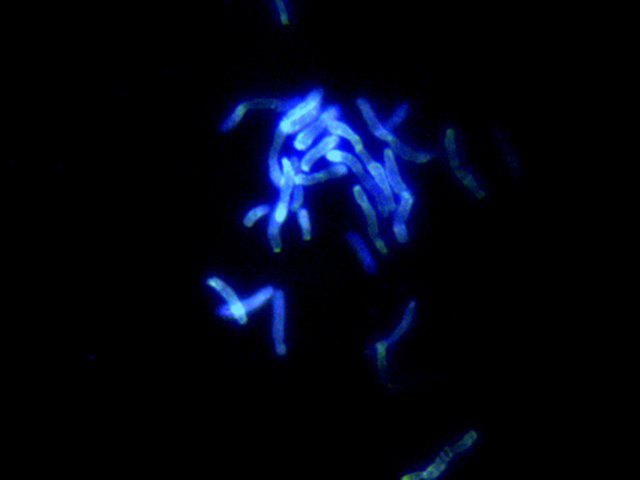

花斑癣处皮屑里的马拉色菌

治疗方法:以局部治疗为主。可选用各种外用抗真菌药物(首选酮康唑、克霉唑、联苯苄唑、舍他康唑等唑类药物)进行治疗,每天1-2次,疗程2-4周。皮损范围大或外治疗效不佳时考虑内服药物。首选伊曲康唑等。